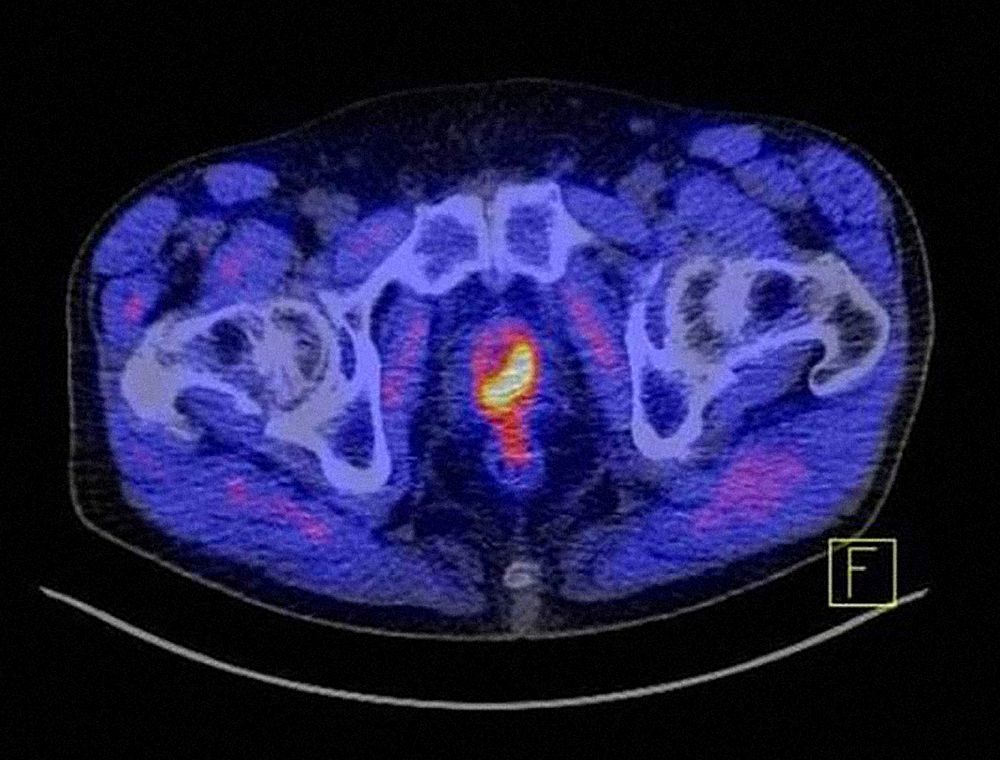

Mit dem PSA in Verbindung steht das Prostata-spezifische Membran Antigen (PSMA). Dieses Molekül ist auf der Oberfläche gesunder Prostatazellen vorhanden, sehr viel mehr aber auf Prostatakrebs-Zellen. Im restlichen Körper kommt das Protein kaum vor. „PSMA ist deshalb ein ideales Zielmolekül für die Diagnostik und zugleich auch für zielgerichtete Therapien von Prostatakrebs“, sagt Prof. Andreas Buck. Der Direktor der Klinik und Poliklinik für Nuklearmedizin des UKW wird beim Infotag der Frage nachgehen, ob ein PET-CT mit PSMA heute schon als Diagnosestandard bezeichnet werden kann.